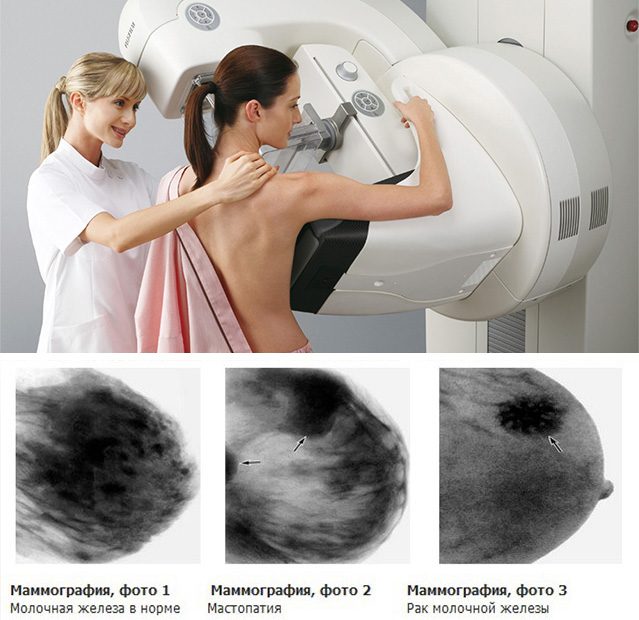

Феномен гипердиагностики в маммографии: примеры и иллюстрации

Раздел: Образы вокруг